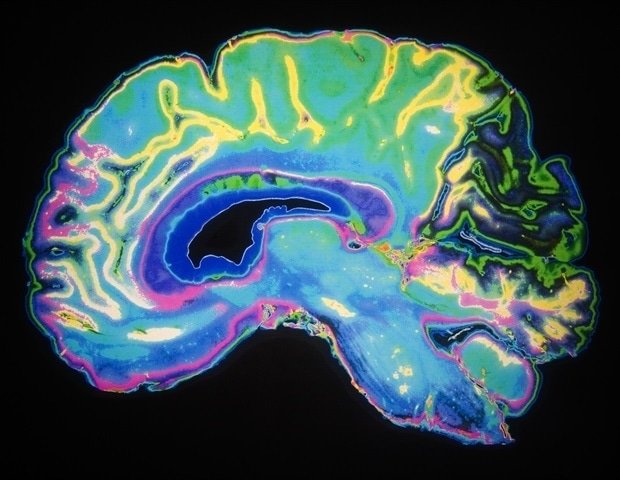

The human brain, our most complex organ, functions as a network of interconnected modules specialized for tasks such as color perception and face recognition. Previous studies have found that these modules become less specialized with age and that their dysfunction is associated with poor memory and other cognitive decline.

Much remains unknown about the chemical and cellular mechanisms underlying this age-related decline in brain function, and how genes, lifestyle, environment, and medicine alter its trajectory. To uncover this mystery, in the new study, researchers used a non-invasive technique called functional magnetic resonance imaging (fMRI) to scan the brains of 82 mice at several intervals from 3 to 20 months of age, roughly equivalent to a human age of 18 to 70.

fMRI is an imaging method that detects changes in blood flow to the brain. But the mouse brain is about 3,000 times smaller in volume than a human brain, so the researchers needed a special strategy for imaging. For example, scientists used fMRI scanners with magnetic fields more than three times stronger than those commonly used by humans, allowing them to image finer details.